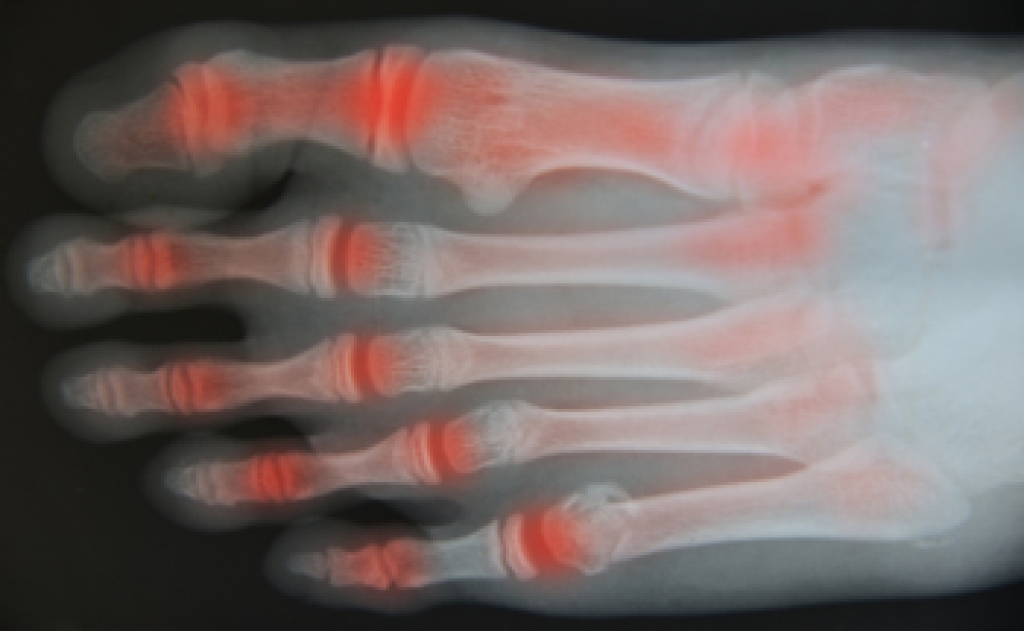

Gout is a type of arthritis caused by a buildup of uric acid in the bloodstream. It often develops in the foot, especially the big toe area, although it can manifest in other parts of the body as well. Gout can make walking and standing very painful and is especially common in diabetics and the obese.

Gout can easily be identified by redness and inflammation of the big toe and the surrounding areas of the foot. Other symptoms include extreme fatigue, joint pain, and running high fevers. Sometimes corticosteroid drugs can be prescribed to treat gout, but the best way to combat this disease is to get more exercise and eat a better diet.